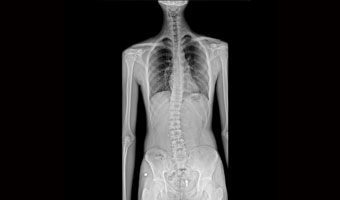

Klinik Vakalar

Tam klinik uygulama, her yerde bakım

Ortopedik yaralanmalar

Tek çekimde tam omurga ve alt ekstremite görüntüleme.

Ergen skolyozu ve geleneksel göğüs röntgeni taraması.

Uygulama Görüntüleri

Tıbbi tarama